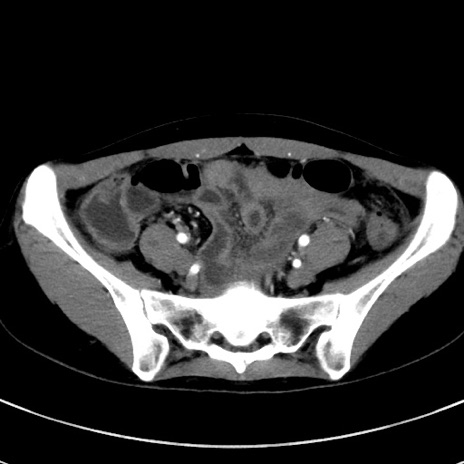

症例17(横断像)

【症例】20歳代女性

【主訴】嘔吐、下腹部痛

【現病歴】昨日夕食後に嘔吐し下腹部痛が出現。本日になっても嘔吐持続し改善しないため来院。

【身体所見】意識清明、BT 37.2℃、BP 108/67mmHg、腹部:平坦、やや硬、下腹部正中から右にかけて圧痛あり、反跳痛軽度あり、tapping pain(+)。

【データ】WBC 13600、CRP 14.94

冠状断像